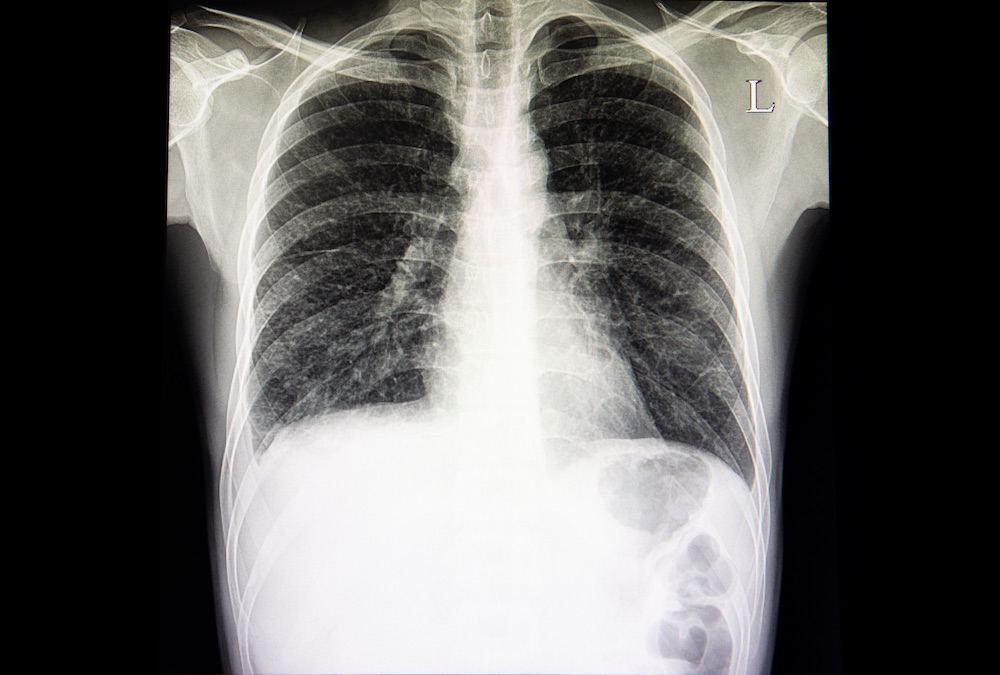

Rhumatisme psoriasique : un surrisque de pneumopathie interstitielle sous biothérapie

Les patients atteints de rhumatisme psoriasique débutant un traitement de fond biologique ou synthétique ciblé présentent un risque accru de développer une pneumopathie interstitielle par rapport à la population générale, selon une étude présentée au congrès de l'European Alliance of Associations for Rheumatology (EULAR).